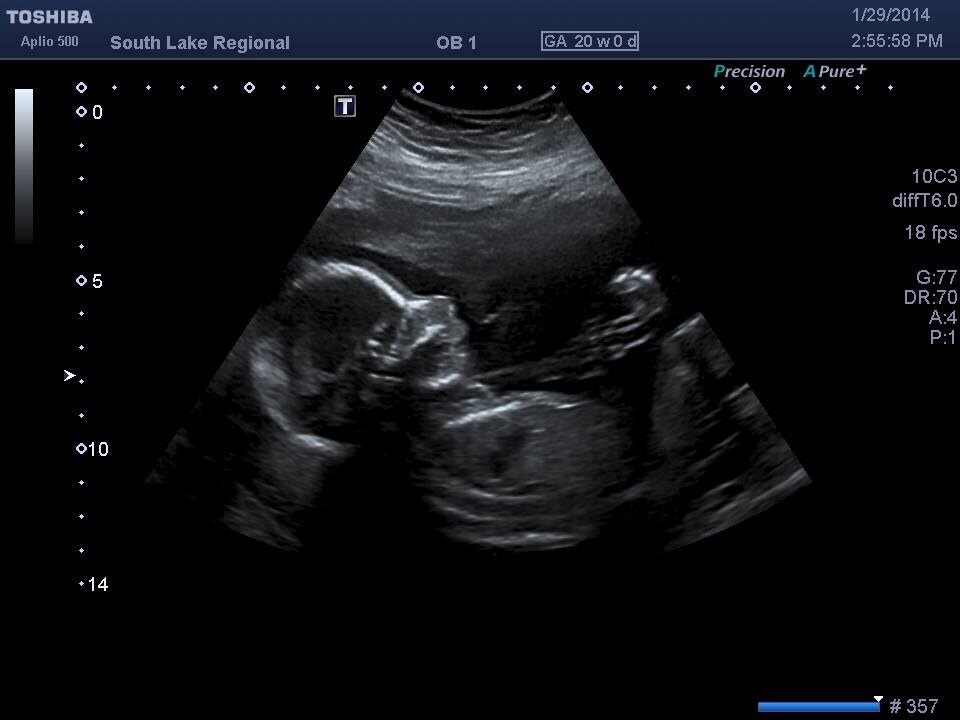

Hi can you predict what I'm havinghttp://img.tapatalk.com/d/14/02/21/tynu6epa.jpg

Sent from my iPhone using Tapatalk